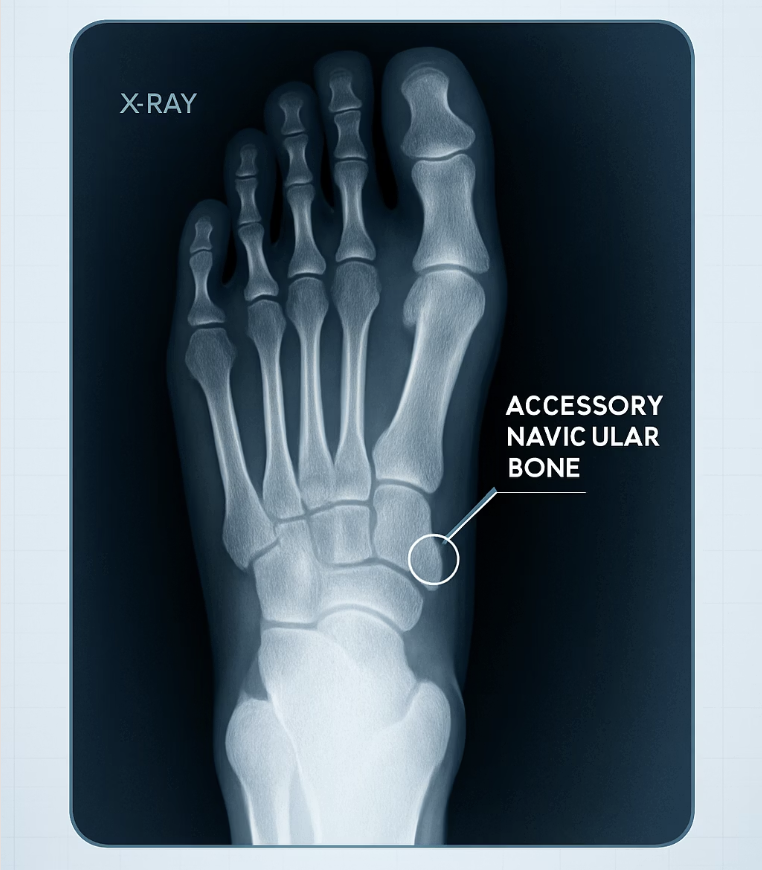

특히 발 안쪽 복숭아뼈 바로 아래가 툭 튀어나와 있고, 그 부위를 누르면 통증이 심하다면 ‘부주상골 증후군’을 의심해 볼 수 있습니다. 부주상골은 일부 사람들이 선천적으로 가지고 태어나는 ‘없어도 되는 덤 뼈’입니다. 평소에는 아무 문제 없다가, 발에 꽉 끼는 신발을 신거나 과격한 운동을 하면서 이 덧뼈에 붙어있는 힘줄이 자극을 받아 염증이 생기는 것이죠.

이 경우, 통증을 유발하는 가장 큰 원인은 ‘마찰’과 ‘압박’입니다. 따라서 발 안쪽을 강하게 압박하는 신발을 피하고, 발바닥의 아치를 받쳐주는 기능성 깔창을 사용하여 덧뼈에 가해지는 부담을 줄여주는 것이 효과적인 해결책입니다. 통증이 지속된다면 정확한 진단을 위해 병원을 방문하는 것이 좋습니다.